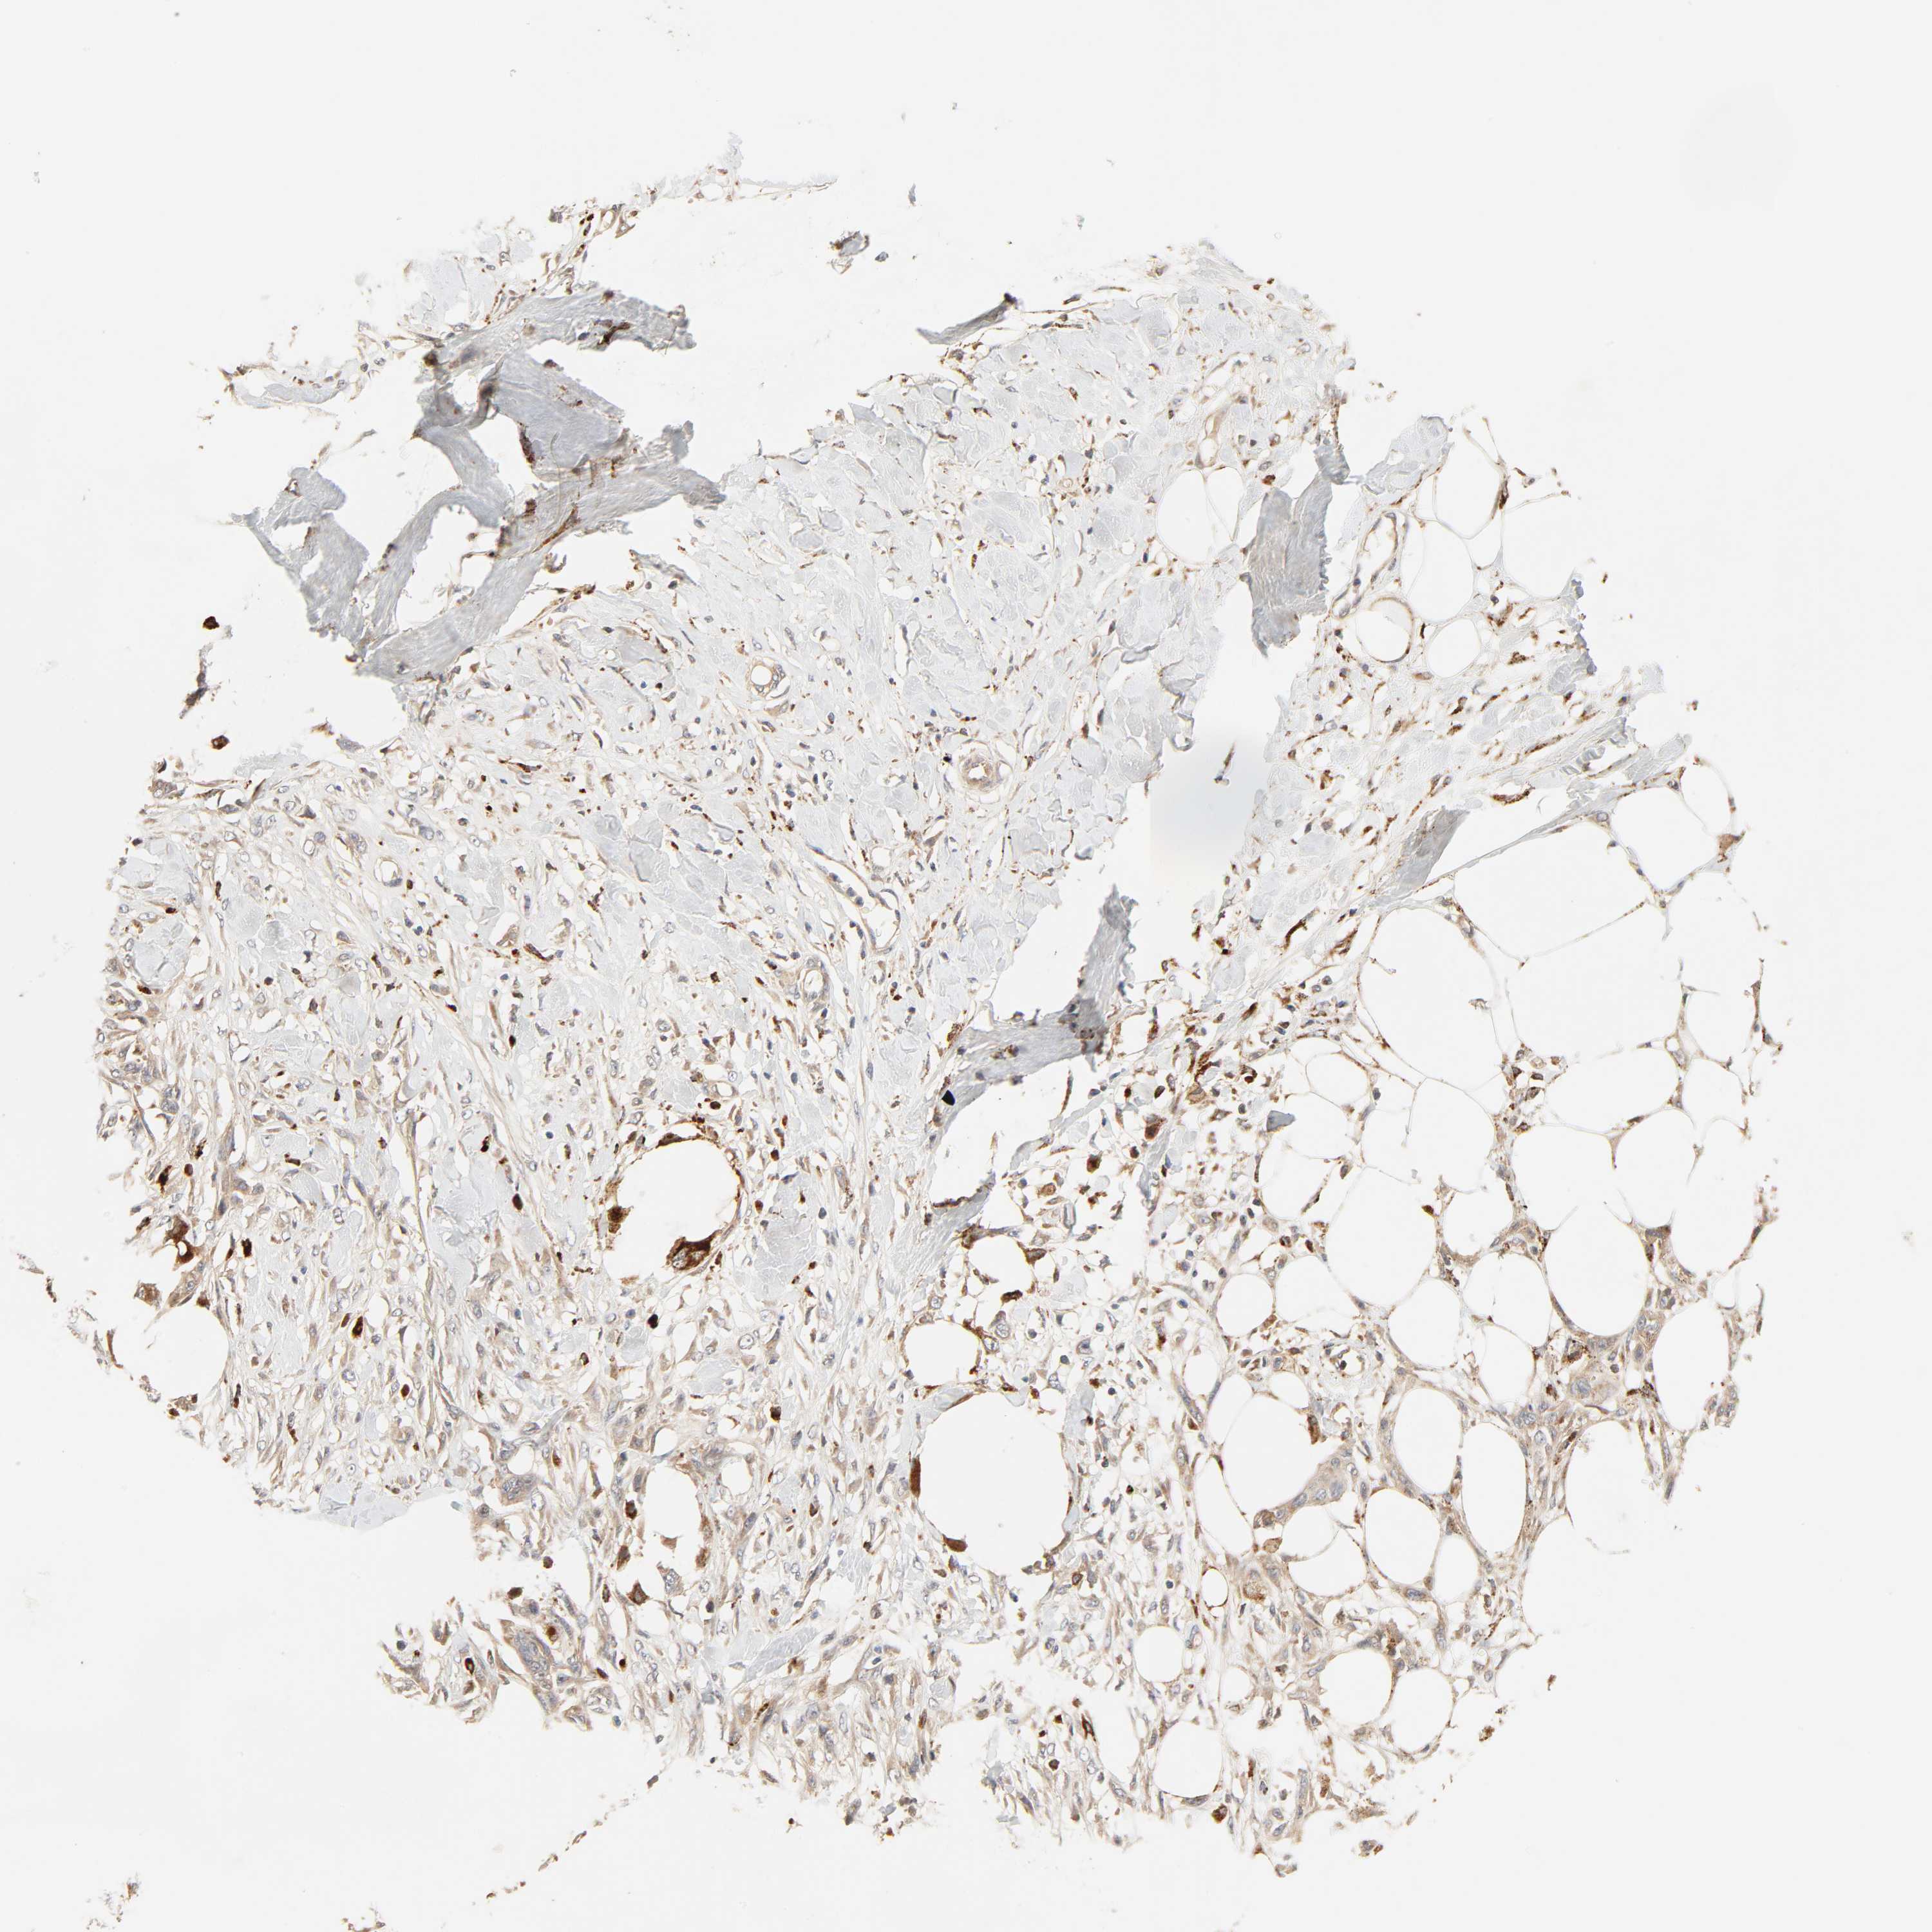

SKIN CANCER - Protein expressioni

A mouse-over function shows sample information and annotation data. Click on an image to view it in a full screen mode. Samples can be filtered based on level of antibody staining by selecting one or several of the following categories: high, medium, low and not detected. The assay and annotation is described here.

Antibody stainingi

Antibody staining in the annotated cell types in the current human tissue is reported as not detected, low, medium, or high, based on conventional immunohistochemistry profiling in selected tissues. This score is based on the combination of the staining intensity and fraction of stained cells.

Each image is clickable and will lead to virtual microscopy that enables deeper exploration of all samples and also displays staining intensity scores, fraction scores and subcellular localization as well as patient and tissue information for each sample.

Antibody HPA030262

Basal cell carcinoma